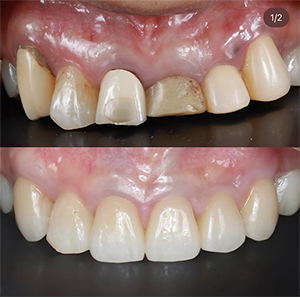

• case02

02のサムネイル